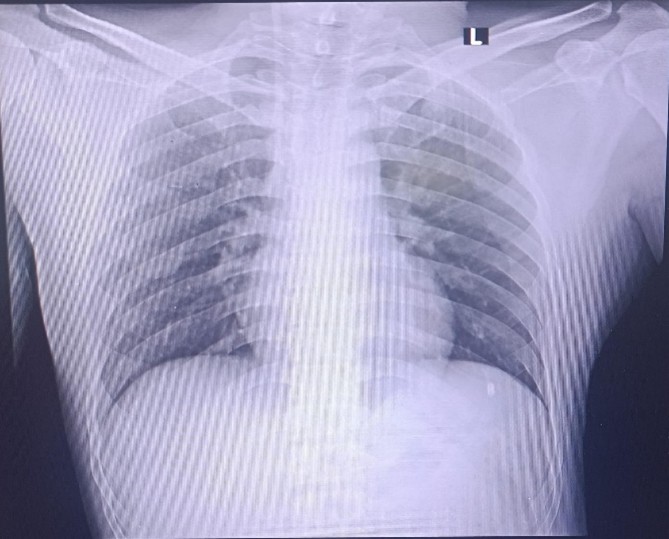

Chest X-Ray